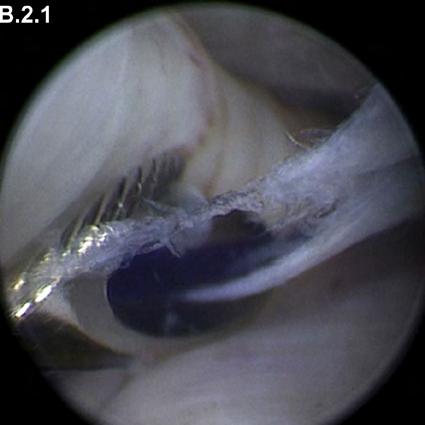

En el Journal of Oral and Maxillofacial Surgery Dr. Daniel Jerez publica adaptación a la técnica de discopéxica de Yang

El Dr. Daniel Jerez, cirujano maxilofacial y Subdirector Académico de Clínica Bupa Santiago, publicó en el mes de julio, en la prestigiosa revista especializada Journal of Oral and Maxillofacial Surgery (JOMS), un artículo que describe una modificación a la técnica de discopéxica del Dr. Yang (China).

El paper que realizó en conjunto a los doctores German Laissle, Carlos Fuenzalida y Sergio Uribe , tiene por nombre “Modification to Yang’s Arthroscopic Discopexy Technique for Temporomandibular Joint Disc Displacement: A Technical Note”, y ahonda en la adaptación a esta técnica, donde se realiza una doble sutura para efectuar la recaptura discal o discopexia.

Respecto a la técnica antes mencionada, el Dr. Jerez manifestó que “es compleja artroscópica, mínimamente invasiva y tiene como objetivo principal devolver la función articular, evitar la progresión de la osteoartrosis, reducir el dolor y mejorar la dinámica mandibular. Esta técnica se realiza muy poco, pues técnicamente es muy difícil llevarla a cabo y además requiere instrumental específico”.

DR. DANIEL JEREZ Cirujano Maxilofacial Subdirector Académico Clínica Bupa Santiago

Puntualmente, la modificación sugerida por el cirujano maxilofacial de Clínica Bupa Santiago dice relación con llevar a cabo esta técnica, pero sin necesidad de utilizar un instrumental determinado, lo cual según expresa “es mucho más estable a largo plazo y ha demostrado mejores resultados en la evidencia, ya que al ser artroscópica es una cirugía mínimamente invasiva, poco riesgosa y sin cicatriz”.

Para revisar el detalle de esta publicación y en qué consiste la modificación, los invitamos a hacer clic aquí.